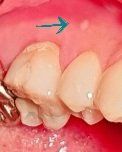

잇몸에 있는것은 직접 봐야 알 수 있을것으로 보입니다. 역시 포디스과립일수도 있고, 누공일수도 있습니다.

특히 2번째 사진 보면 가장자리는 약간 붉게 보이고 전체적으로 희게 보이는 부위는 것은 염증이 아무는 과정에서

각화층이 생긴 것입니다. 좁쌀 같이 같은 것은 잇몸 형태에서 원래 약간 불규칙하게 나온 것으로 그냥 두면 됩니다.

사진으로만 봤을 경우에는 궤양일수도 있고 치아 뿌리 끝애 염증이 생겨서 잇몸위로 올라온것일수도 있습니다.